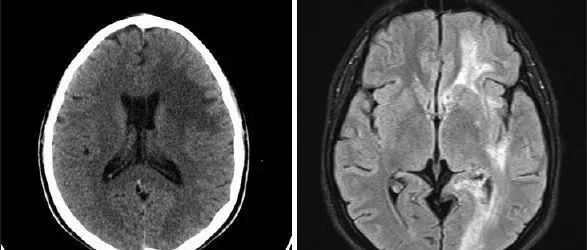

35岁女性,在2次右手局灶性感觉性发作后至医院就诊,其中第2次发展为全面性强直阵挛发作。查体未发现运动或感觉缺陷。MRI可见显示5个幕上病变,最大的2个为囊性病变——左侧中央后回上外侧30×30×32mm和右侧中央后回外侧7×9×6mm。所有病变均为T1低信号和T2高信号,周围有轻度血管源性水肿(图1A和C)。2个囊性病变呈周围强化、FLAIR高信号,且没有弥散限制(见图1B和D)。(图:MRI可见显示5个幕上病变,最大的2个为囊性病变——左侧中央后回上外侧30×30×32mm和右侧中央后回外侧7×9×6mm[A-D];病变呈T1低信号[A]和T2高信号,周围有轻度血管源性水肿[C];其在FLAIR上呈高信号[C],周围中度强化[B],无弥散受限[D];左侧中央后回上外侧病灶活检组织病理学显示脱髓鞘伴有囊性变和明显的星形胶质细胞增生[E],血管周围淋巴细胞成套[F],无残留髓鞘[G],CD163+巨噬细胞[H],以及大量反应性星形胶质细胞[I])...